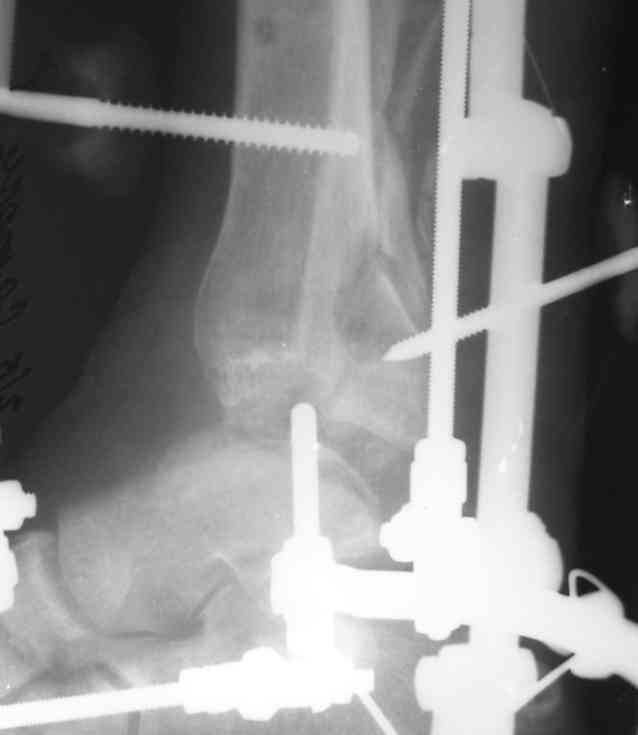

В понедельник в операционной выполнена санация раны с резекцией всех участков кости выступающих в просвет раны, удалены свободнолежащие фрагменты, некрэктомия. Промыто и заполнено салфеткой с некролитической мазью. Дополнительно проведена спица в с/3 голени. "Вытянул" голень до анатомичекой длины. После операции получил неприятный "сюрприз" - дистальный фрагмент б/б кости "разнесло". Снимки выложу завтра. Думаю опять ослабить дистракцию с целью собрать "в кучку" отломки дистального фрагмента, а также для

уменьшения раневой полости (которая меня, по-правде говоря, ужасает).

Состояние раны: постепенно очищается, заполняется грануляциями с участками фибрина. Воспаление мягких тканей вокруг раны купировано. В глубине раны, ближе к дистальному отломку, остается небольшой "гнилой угол" с весьма скудным отделяемым. Две "большие" перевязки в течение недели, с частичными некр- и секвестрэктомиями в условиях операционной.

При закрытой попытке поймать и собрать отломки дистального фрагмента спицами с напайками, удача покинула меня.:-(

Срепонировать суставную поверхность мне не удалось. Только зря прошил ткани, а отломки остались в прежней позиции. Так и подмывало провести спицу через ахилл ... или пойти открыто задним доступом и притянуть винтом. Но смущает один момент: на чем будет держаться резьбовая часть винта, если передная поверхность разбита в хлам? Винт будеть елозить и не даст должной копрессии. Есть ли резон, при нынешнем состоянии раны, пойти на открытую репозицию заднего отдела суставной поверхности?